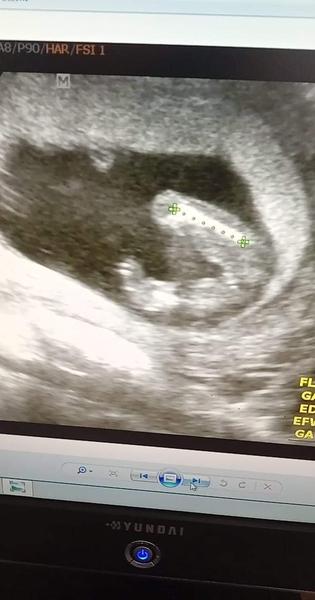

@barulilinka kluk, cekam take kluka a tohle je nas snimek

@barulilinka nemate zac. To ze to bude kluk mam potvrzene od 2 doktoru + uz u 1. Screeningu rekli na 60% kluk. Jelikoz se fotky temer nelisi, tak gratuluji 😁 mate taky kluka

Kluk 😁naše holka tam nic nemá 🤔mrkni do alba.